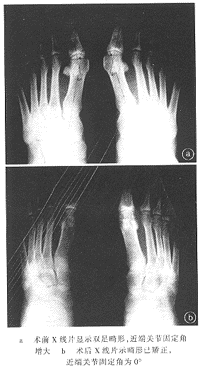

本组17例31足,术后近期无一例出现并发症,第一跖骨截骨均在2个月内愈合,未出现延迟愈合及跖骨头缺血性坏死(图3)。随访1~8年,平均4年5个月,疗效优者10例19足,良者6例11足,优良率达96.8%;术后畸形复发、疗效差者1例1足,其术前跖骨间角16°,术后未矫正。

图3 双足踇外翻畸形手术前后X线表现

术后X线测量结果显示,踇外翻角25°~10°,平均14.3°,较术前平均减小15°;近端关节固定角20°~0°,平均1.95°,较术前平均减小17°;第一跖骨间角15°~0°,平均5.8°,较术前平均减小5°。